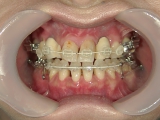

上の歯と下の歯を斜めに繋ぐようにツインフォースという装置を装着します。装置の力で、顎が前方へ押し出されてきました。

顎の移動が終了しました。装置を外して、今後はワイヤーを使用して歯列を治します。